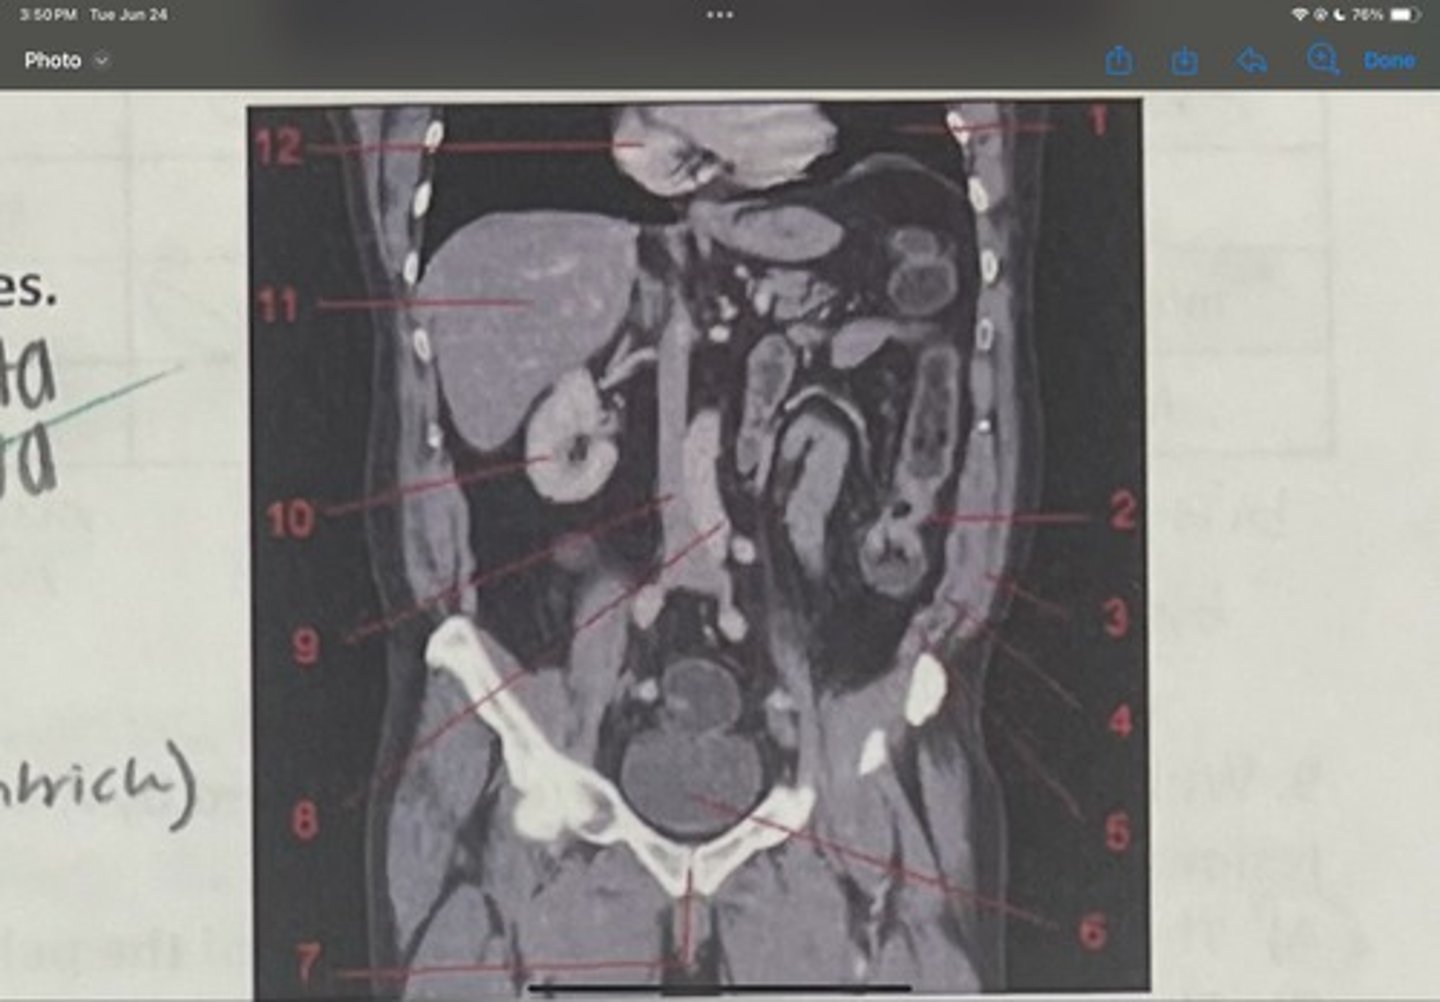

What is 1

Descending colon

What is 2

External oblique

What is 3

Internal obliques

What is 4

Transversus abdominis

What is 5

Bladder

What is 6

Pubic sysmphysis

What is 7

Abdominal aorta

What is 8

Inferior vena cava

What is 9

Right kidney

What is 10

Liver

What is 11

Heart (right ventricle)

What is 12

Subcostal nerve (T12)